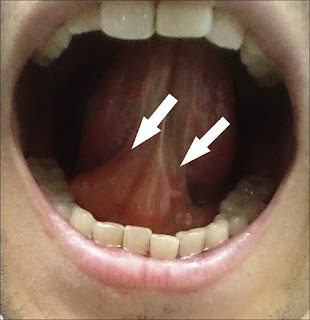

​​​​此為舌下水腫的現象,一般會慢慢改善消腫